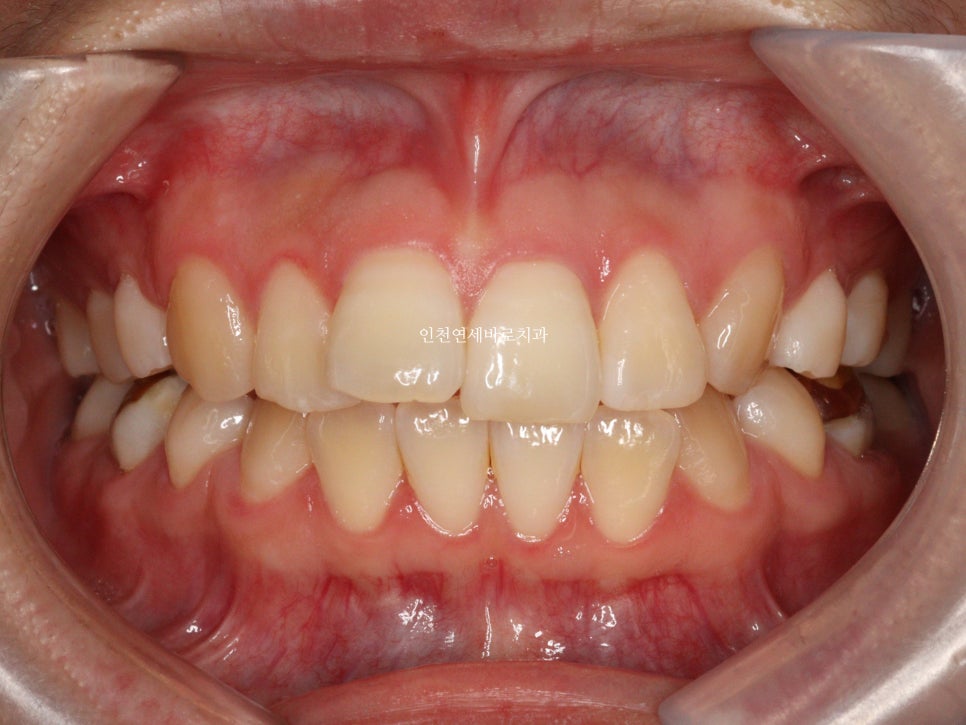

그리고 치료가 마무리 된 후의 모습입니다.

부분교정으로 앞니만 철사를 붙여서도 비슷한 효과를 볼 수 있었을지 모릅니다.

하지만 치아의 삭제가 많은 양 동반되지 않았다면 앞니가 분명 뻗쳐나왔을것입니다.

하지만 인비절라인은 전체교정에 준하는

치아와 주변조직에 무리가 되지 않는 범위에서의 확장을 만들어낼 수 있어

앞니의 뻗침을 최소화 할 수 있는 장점이 있습니다.

위 환자분의 재교정 치료기간은 약 7개월입니다.

7개월동안 병원은 두번 왔구요.